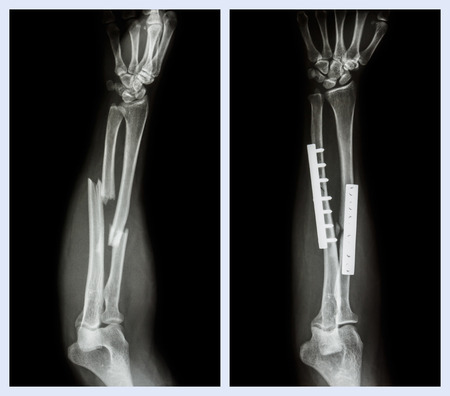

前腕の骨折骨のコレクションです整形外科医の運営と内部固定プレートとスクリュー 1人のストックフォトや画像を多数ご用意 Istock

前腕の骨幹部骨折 一般社団法人 日本骨折治療学会 骨折の解説

上の画像 尺骨骨折と半径 前腕の骨 下の画像 それ運営されて 内部のプレートとスクリュー固定 の写真素材 画像素材 Image

前腕の骨を骨折します それ運営されて 内部のプレートとスクリュー固定 左の画像 操作の前に右画像 操作後 の写真素材 画像素材 Image